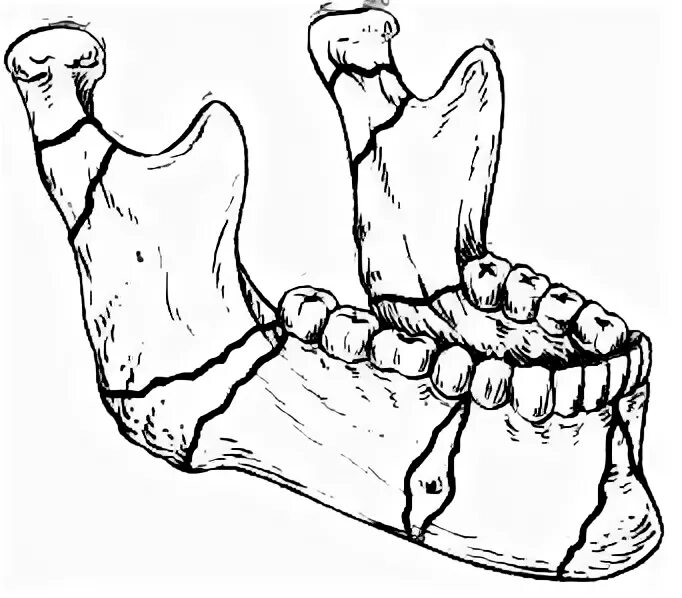

Переломы челюстей студфайл